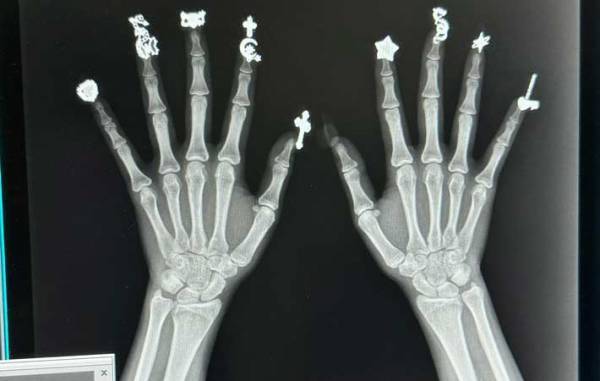

院内を和やかにした実際のレントゲン写真がこちら!

なんと、レントゲン写真にりんあさんのネイルが鮮明に写っているではありませんか…!

レントゲン写真は自分の骨とはいえ、見るのは不安で怖いもの。

しかし、こんなにも『映えた』レントゲン写真が撮れると、不安な気持ちも晴れそうですね!

投稿には10万件以上の『いいね』とたくさんのコメントが寄せられました。

りんあさんによると、幸いにも骨折はしていなかったそうで、薬で治療しているとのことです。

ファンシーすぎるレントゲン写真は、りんあさんはもちろん、診察を担当した医師や看護師にとっても記憶に残る特別なものとなったことでしょう!